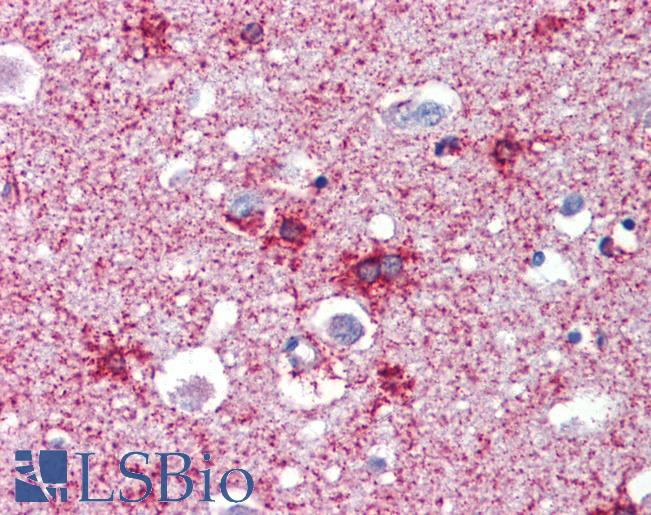

IHC Results Paraffin embedded Human Breast, Tonsil and Brain (Cortex). Recommended concentration: 2.5µg/ml. | |